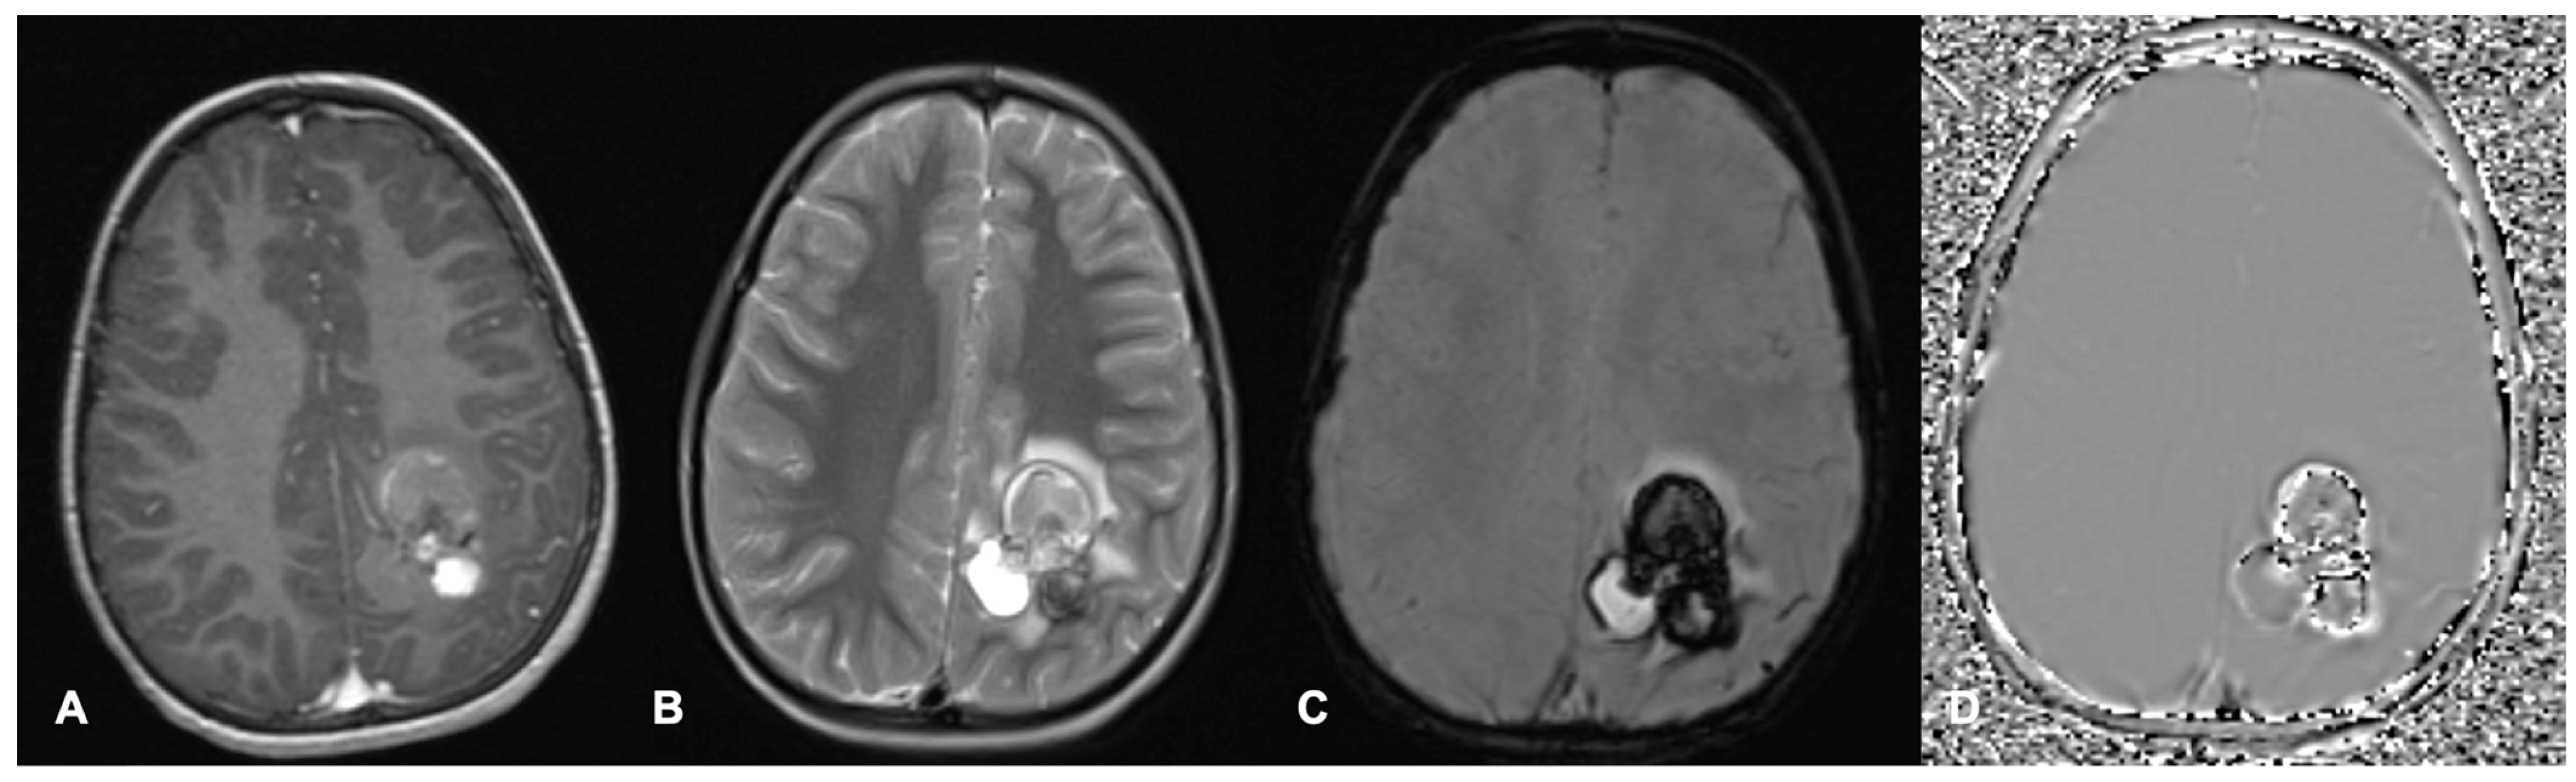

- Nowak, J.; Jünger, S.T.; Huflage, H.; Seidel, C.; Hohm, A.; Vandergrift, L.A.; von Hoff, K.; Rutkowski, S.; Pietsch, T.; Warmuth-Metz, M. MRI Phenotype of RELA-fused Pediatric Supratentorial Ependymoma. Clin. Neuroradiol. 2019, 29, 595–604. [Google Scholar] [CrossRef]